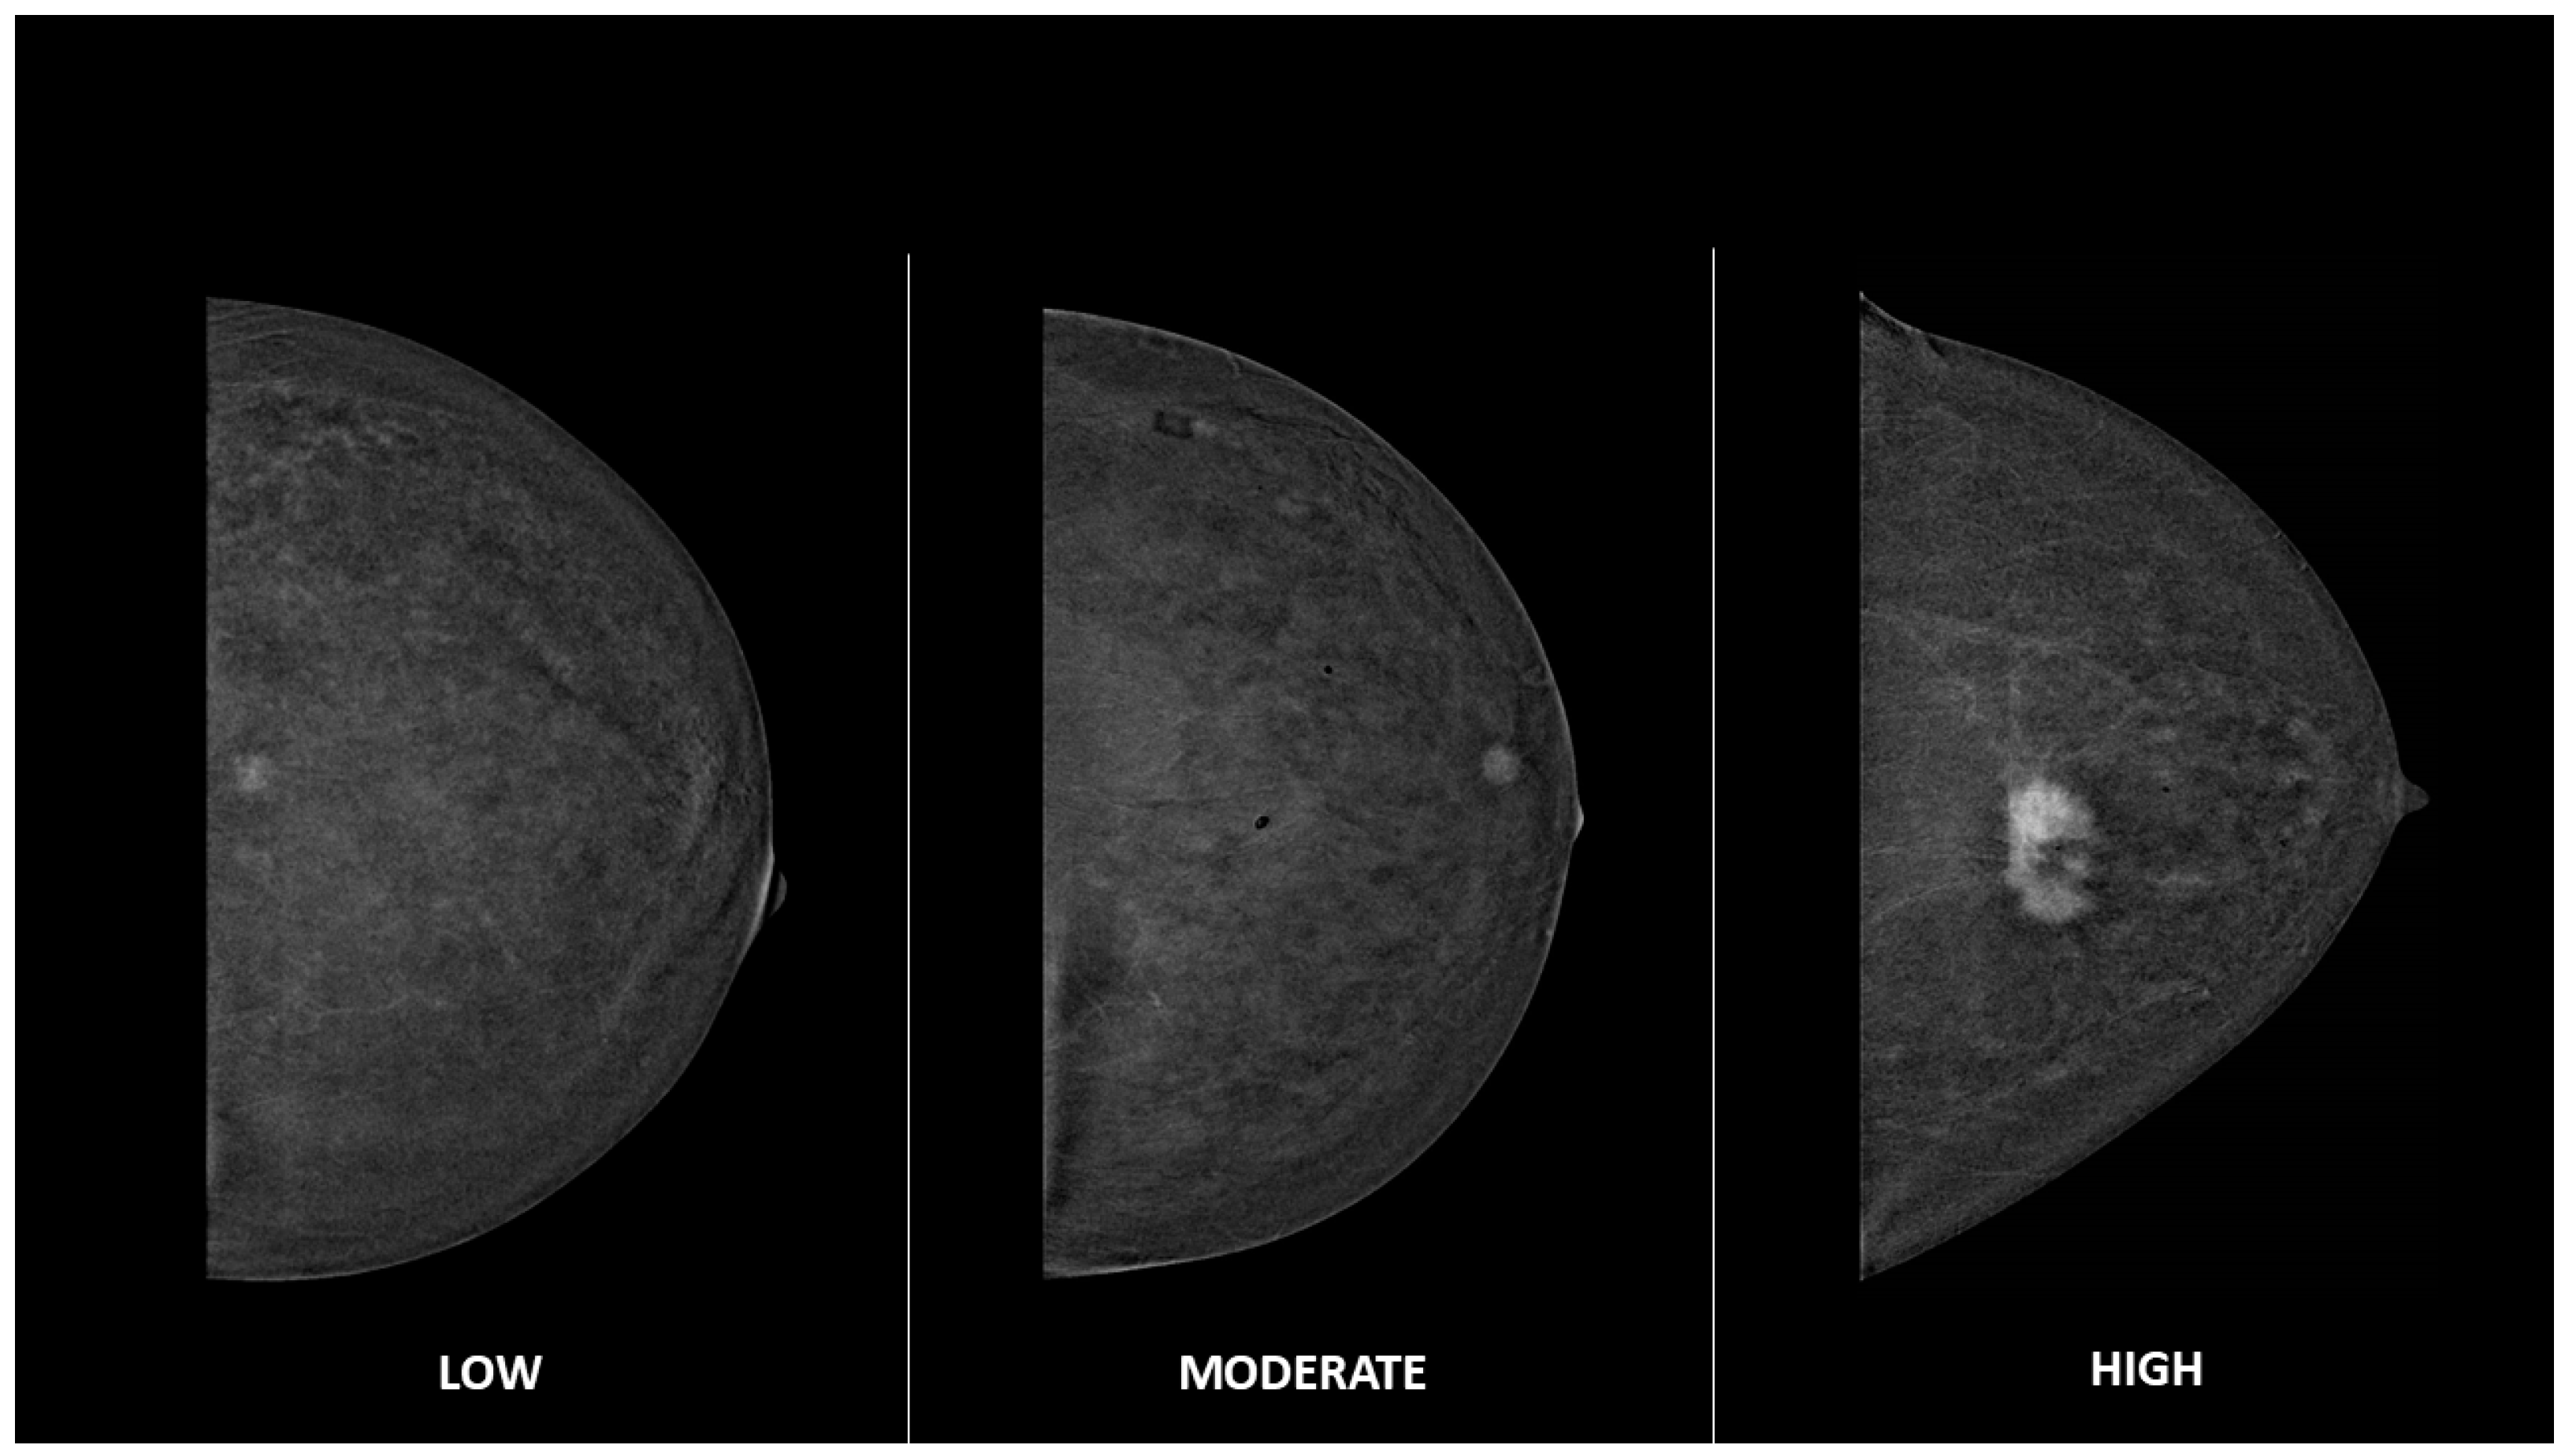

2.4. Image Analysis